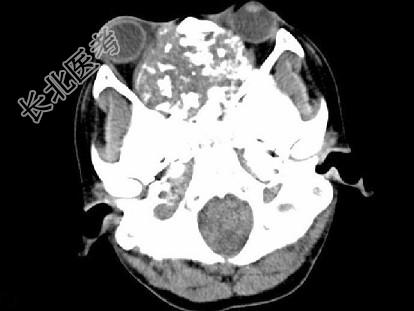

- 单项选择题男,26岁, 进行性鼻腔阻塞、流涕来院就诊,近两年持续性头痛、头晕, 筛窦区病变影像检查如图,最可能的诊断是 ( )